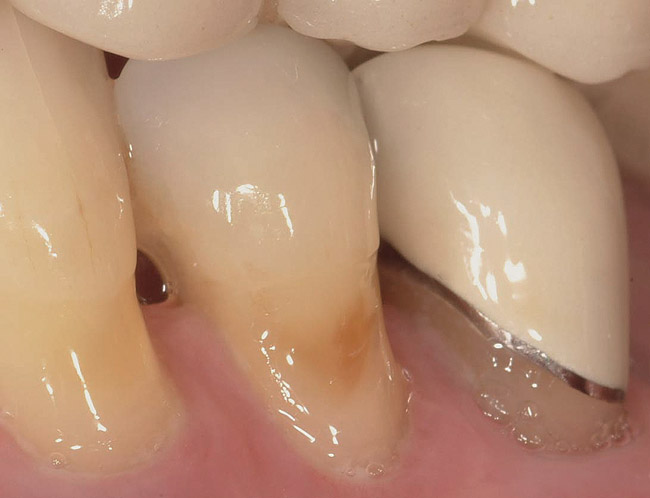

A patient with Stage 1 demineralization (Figure 2) presents with exposed root surfaces that appear dull when dried and illuminated. When palpated with the side of the explorer, the root surface feels rough and slightly soft to pressure from the side of the explorer. Color changes associated with D1 root-surface lesions may range from no color change to a darkening of the yellow color of the cementum. There is no cavitation of the root surface, and these patients may be unaware of the gingival recession occurring in their mouth. Although some patients may not present with specific concerns related to gingival recession, many patients present with sensitivity to cold and a negative perception of esthetics in the recession areas. The recommended treatment for D1 root-surface lesions includes remineralization with products (pastes and varnishes) containing fluoride, calcium, and phosphate. It is the experience of the authors that remineralization of root surfaces is often coupled with a marked decrease in sensitivity. In addition, it is critical for the clinician to determine the cause of the gingival recession to prevent the worsening of the condition.

Stage 2 Demineralization (D2)

Figure 2  The root surface cervical to the crown margin appears darker than healthy cementum. In addition, the surface appears dull. When palpated with the side of an explorer, the clinician can expect to feel a root surface that resists the explorer over its surface.

Figure 2